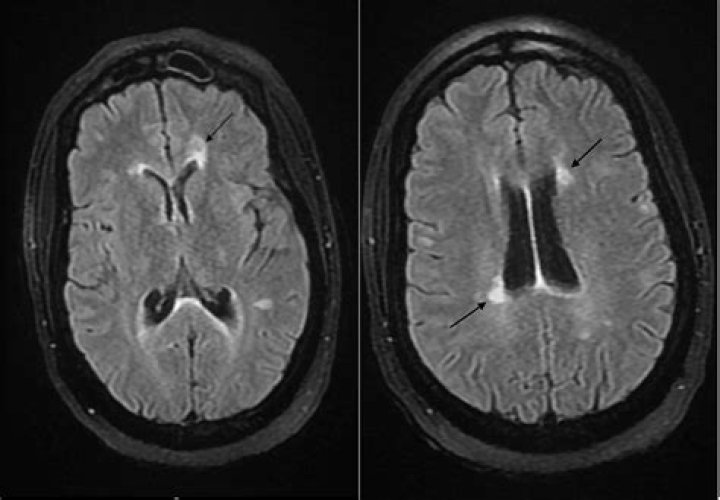

In MS, demyelination occurs in the white matter of the brain and in the spinal cord. Lesions or “plaques” then form where myelin is under attack by the immune system. Many of these plaques (or scar tissue) occur throughout the brain over the course of years.